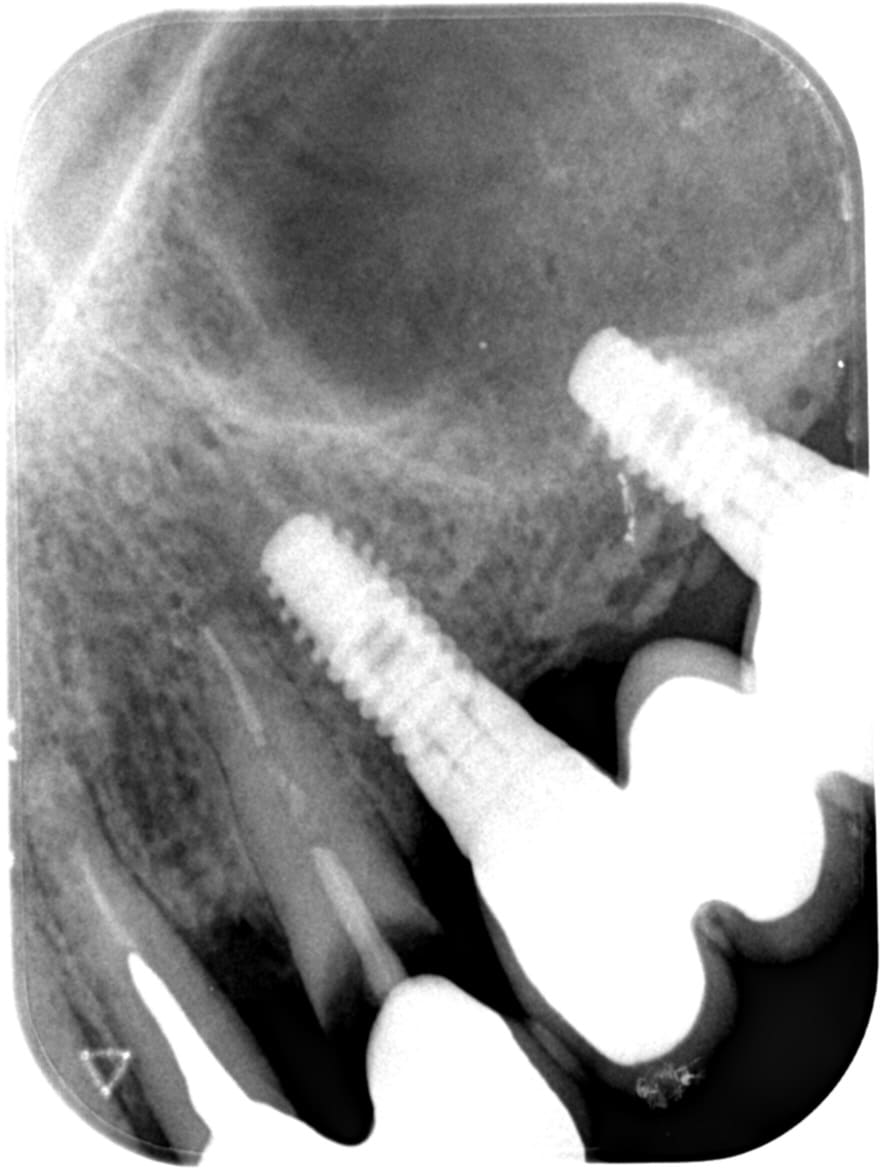

22 et 23 ont clairement des pêches, c’est une contrindication pour une implantation immédiate, alors pour une mci, encore plus.

et planter ton clou dans le site de 22 infecté..... c'est généralement dans ces cas là que çà merde le plus facilement....on est jamais sûr à 100% d'avoir tout viré le tissus de granulation....

Concernant une EIIMEI dans un secteur un peu infecté, j'en ai fais un paquet, ça se passe tj bien.

Voir la technique IDR, implantation immédiate dans de grosses lésions, avec reconstruction osseuse. J'ai quelques cas bien corsés, qui se passent fort bien !

Des cas de mise en charge immédiate sur site où je vire des pêches avant, j’en ai plein. Jamais eu de soucis.

Par contre faut être méticuleux au curetage…